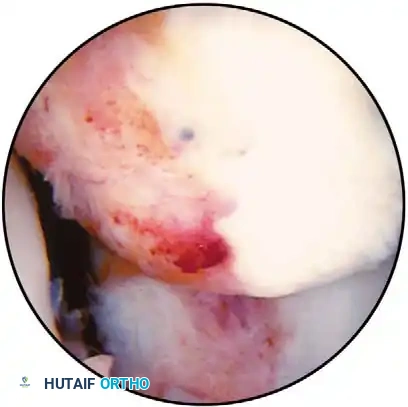

Fig. 48-9 A, Complete tear of anterior cruciate ligament. B, Horizontal tear of degenerative lateral meniscus. C, Oblique tear of posterior horn of lateral meniscus. D, Incomplete radial tear of lateral meniscus. E, Degenerative tear of lateral meniscus. F, Resection of tear of lateral meniscus. Remaining tissue shows fatty degeneration.

Oblique tears are full-thickness tears running obliquely from the inner edge of the meniscus out into the body of the meniscus. If the base of the tear is posterior, it is referred to as a posterior oblique tear (see Fig. 48-9C); the base of an anterior oblique tear is in the anterior horn of the meniscus (Fig. 48-13). Radial tears, similar to oblique tears, are vertically oriented, extending from the inner edge of the meniscus toward its periphery, and can be complete or incomplete (see Fig. 48-9D), depending on the extent of involvement. These probably are similar in pathogenesis to oblique tears (Fig. 48-14). The possible variations include fl ap tears, complex tears, and degenerative meniscal tears. Flap tears are similar to oblique tears, but usually have a horizontal cleavage element, rather than being purely vertical in orientation. Tears containing a horizontal element often are referred to as superior or inferior fl ap tears, depending on where the fl ap is based on the surface of the meniscus. Complex tears may contain elements of all of the abovementioned types of tears and are more common in chronic meniscal lesions or in older degenerative menisci. These generally are caused by chronic, long-standing, altered mechanics of the meniscus, and the initial tear occurring in the meniscus may not be identifi able after several different planes of tearing have resulted. Degenerative tears often refer to complex tears. These present with marked irregularity and complex tearing within the meniscus (see Fig. 48-9E and F). These are most often seen in older patients.

Horizontal, Oblique, Radial, and Complex Tears In evaluating horizontal, oblique, radial, and complex tears, it is imperative to evaluate and remove only damaged tissue, while maintaining functional, healthy meniscal tissue.

21). Complete radial tears that go to the meniscosynovial junction are diffi cult problems. Some authors believe that horizontal mattress repair of the peripheral portion of the meniscus is indicated because resection would result in loss of the functional protective mechanism of the meniscus. This is discussed further in the section on meniscal repairs.